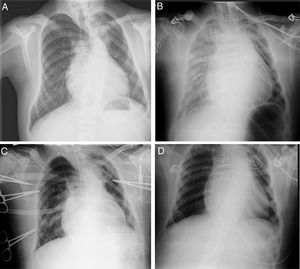

Ingresó en UCIP estable, en ritmo sinusal con PA normal y buena perfusión periférica, en tratamiento con noradrenalina 0,1μg/kg/min y dopamina 5μg/kg/min. En la radiografía de tórax no se observaron complicaciones (fig. 2A). Equilibrio ácido base normal con láctico 1,7mmol/l. Presión venosa10-12. A lo largo de la tarde aparecieron secreciones serohemáticas abundantes que obligaron a aspiraciones frecuentes (30min). Se asoció furosemida y se aumentó la dopamina hasta 7,5μg/kg/min. A las 3h del ingreso comenzó desaturación progresiva y se repitió radiografía de tórax, observándose un derrame pleural derecho severo y colocándose tubo de tórax. Progresivamente se objetivó labilidad hemodinámica, que precisó aumentar noradrenalina a 0,9μg/kg/min. Taquicardia mantenida con aumento progresivo de láctico (máximo 2,9mmol/l). Diuresis en torno a 1,5cc/kg/h. Progresivo empeoramiento de gases pO2 94-79 con una PaO2/FiO2 de 125-128. Se siguió incrementando la FiO2 hasta el 75%. Ante la sospecha de SDRA secundario a reperfusión pulmonar se administra actocortina 100mg. La radiografía de control empeoró progresivamente durante la noche (fig. 2B), con un drenaje pleural derecho severo de contenido seroso. Asimismo, se asoció un deterioro hemodinámico que obligó a aumentar las drogas vasoactivas, disminuyendo la diuresis y aumentando la acidosis: láctico 9,7mmol/l, EB −10pH de 7,18 con FiO2 85% y PEEP de 7.

Ante estos datos se decidió colocación de ECMO venoarterial central (Centrimag®), con un flujo de 3,35lpm 90% del flujo total 505rpm. Se mantuvo inicialmente con noradrenalina a 0,6μg/kg/min, consiguiéndose progresivamente mejorar los datos hemodinámicos y respiratorios (fig. 2C).

Se retiró la asistencia ECMO sin complicaciones, pudiendo ser extubado el día +16 de la cirugía tras mejoría de la tonicidad muscular y buenos parámetros: Gases con vapotherm, FiO2 50%, 10lpm, FR 19, SaO2 99% y mejoría sustancial de la radiografía de tórax (fig. 2D).